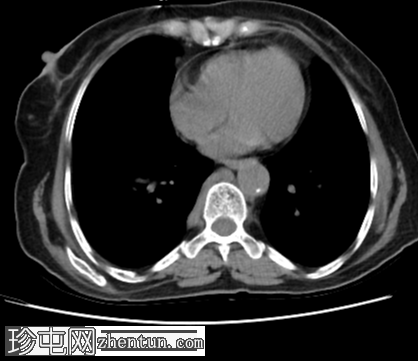

右肾上腺部位可见一个72 x 64毫米大小不规则、边界不清的肿块,侵犯右肾上极、肾上腺下腔静脉(IVC)以及肝7段和6段。脊柱与肿块之间的脂肪平面消失。由于下腔静脉阻塞,奇静脉和半奇静脉扩张。

前纵隔可见两个边界不清的肿块,应排除转移性病变。

此外,上腔静脉(SVC)处有一条中心静脉导管,可用于建立静脉通路。

这些表现与肾上腺皮质癌侵犯肝脏、肾脏、下腔静脉(IVC)及可疑纵隔受累相符。